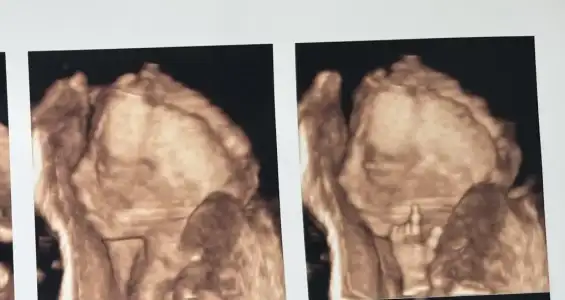

Kızlar merhaba, bayadır yazmıyordum buraya nasılsınız? Her şey yolundadır umarım 🙏🏻❤️ 20+3teyiz bugün, cumartesi günü detaylı ultrasonumuz vardı, çok şükür bir problem yok sağlıklı ilerliyoruz 🤲💗 kızım biraz yordu doktoru pozisyon vermek istemedi 🤣 yüzünü de tam göstermedi inatçı olacak baya galiba 🫢

yaa maaşallah ne güzel görmüşsünüz. Şu parmaklara bak ya ne kadar güzel büyüdü bebişlerimiz böyle görünce insan heycanlanıyor :) Maaşallah :nazar: